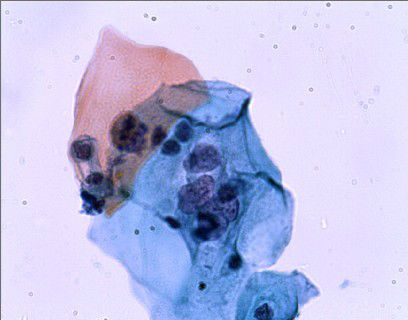

体检,29岁,宫颈轻度糜烂图1

标签:体检 29岁 宫颈轻度糜烂

相当漂亮的PP哦.

ASCUS和LSIL中,我愿选LSIL。

谢谢,看到这样的图片有点激动。核增大异形,核膜不规则,双核细胞,挖空改变,胞浆嗜双色,视觉大餐.